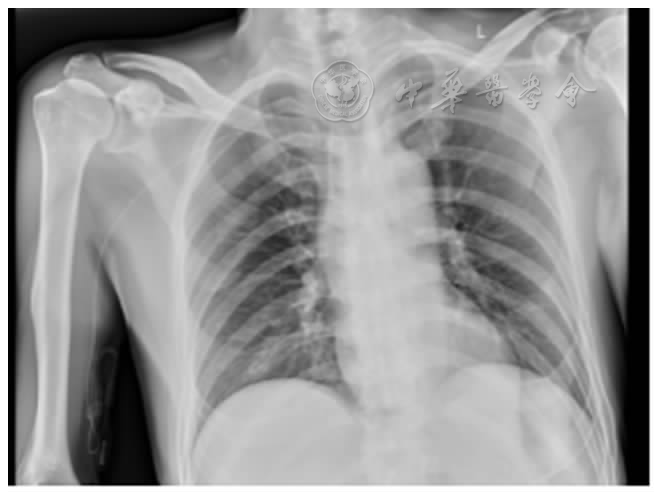

图3 胸片检查导管位置